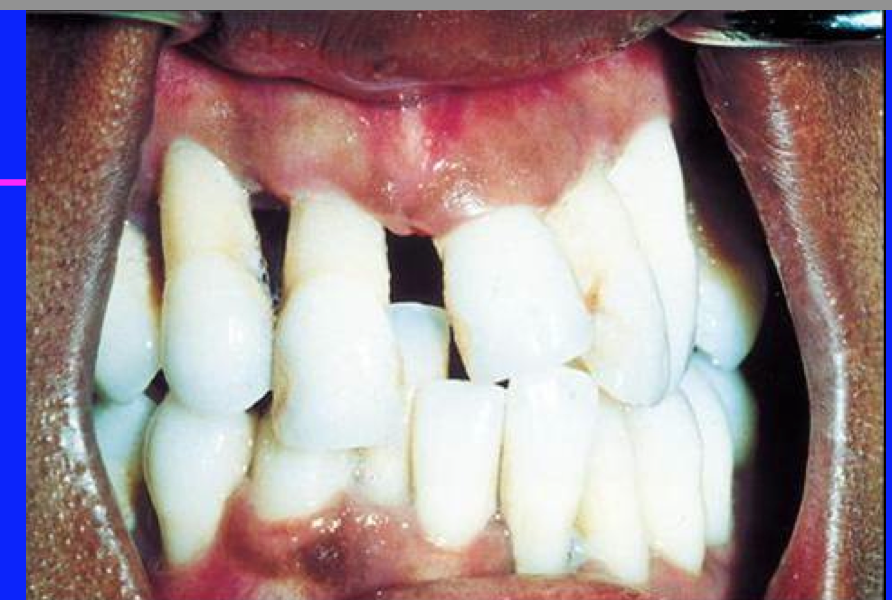

localized juvenille perio

localized juvenile perio